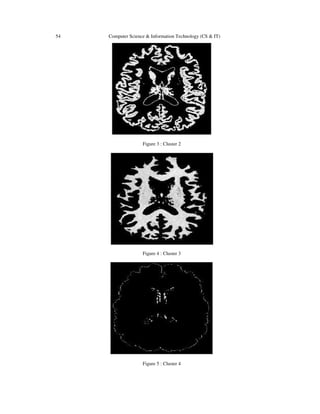

The experiments and performance evaluation were performed on medical images including a CT

image of the MR image of brain The GKFCM clustering and the pro-posed kernel based fuzzy

level set method were implemented with Matlab R2013a (MathWorks, Natick, MA, USA) in a

Windows 7 System Ultimate. All the experiments were run on a VAIO Precision 340 computer

with Intel i3 and 4GB RAM.

Figure 3 : Cluster 2

Figure 4 : Cluster 3

Figure 5 : Cluster 4